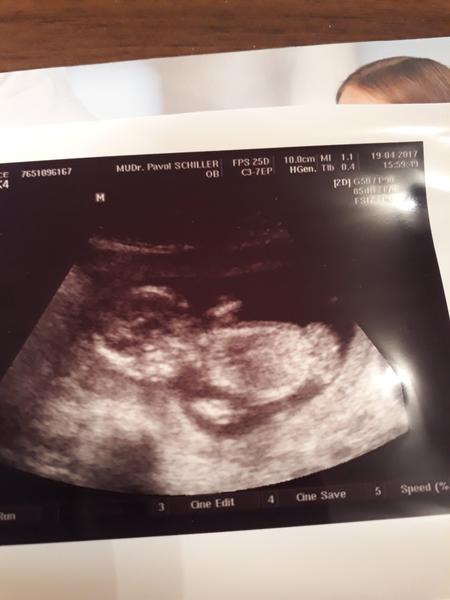

@sofija18 @karmela @luta13 tak dievcata sme podla sona 13+6 CRL mame 7,7 a si predstavte on dnes nameral to NT az 4,2 😐. Povedal ze to nemusi znamenat ze duetatko bude chore no uz ti vrta hlavou. Zajtra bude volat do ruzinova kvoli tym odberom choriovych klkov alebo amnia a bud mi este zavola on zajtra a ak nie mam mu volat ja v piatok. Pohlavie ze este nevidi😑. Babenko na fotke je bruskom dole☺

@miriamn76 krasne ako si tam lezka na brusku (pasie konicky 😉 ) - vidim aj tvaricku - obrysy nosteka, pusinky, bradicku, usko atd...Super fotka a som rada, ze ste v poriadku...Verim, ze drobciatko je uplne zdrave a Ty budes mat len dobre vysledky...Len bud v klude a mysli pozitivne...Pohladkaj brusenko odo mna 😘